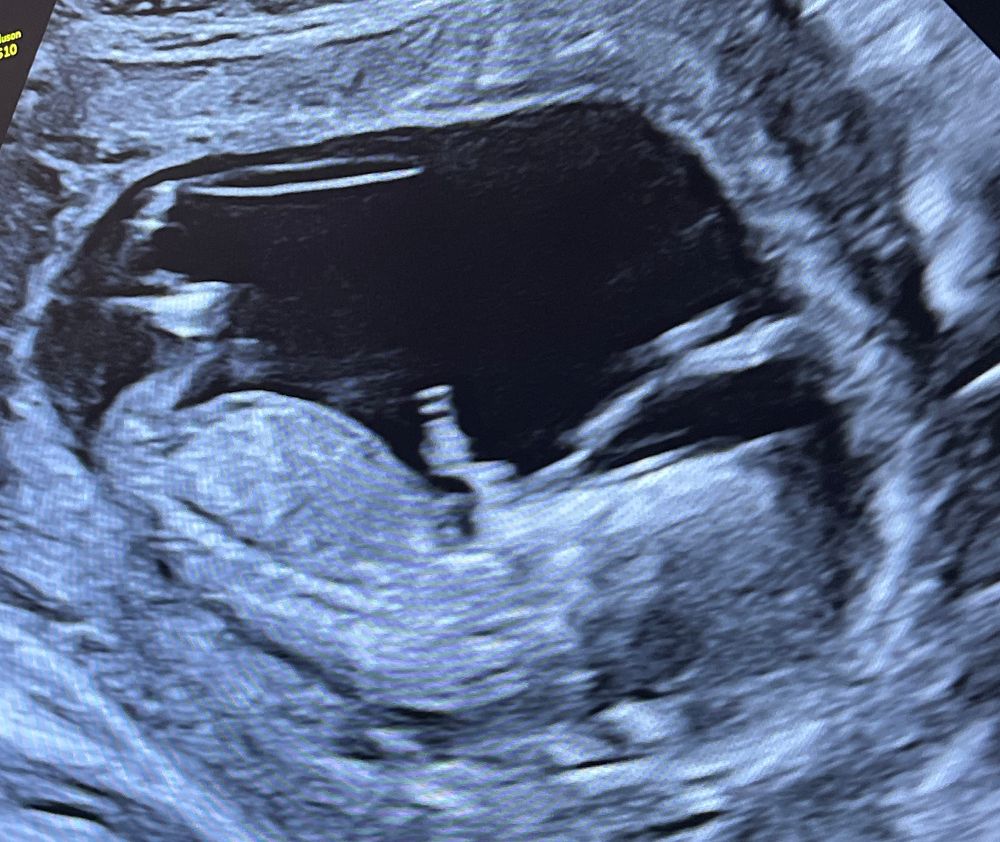

Тут не видно, половой бугорок на этом снимке узи не просматривается

Айсо, ну здравствуйте! Каким образом его может быть видно сквозь ноги? У вас же ребёнок не прозрачный 😄Это просто тень на снимке, но точно не половой бугорок)

Айсо, посмотрела, но тоже нет того ракурса на снимка, ребёнок прячет всё. Потерпите немного, скоро всё узнаете)

Но если нет сил терпеть до 2 скрининга, можно сходить платно на узи по определению пола)